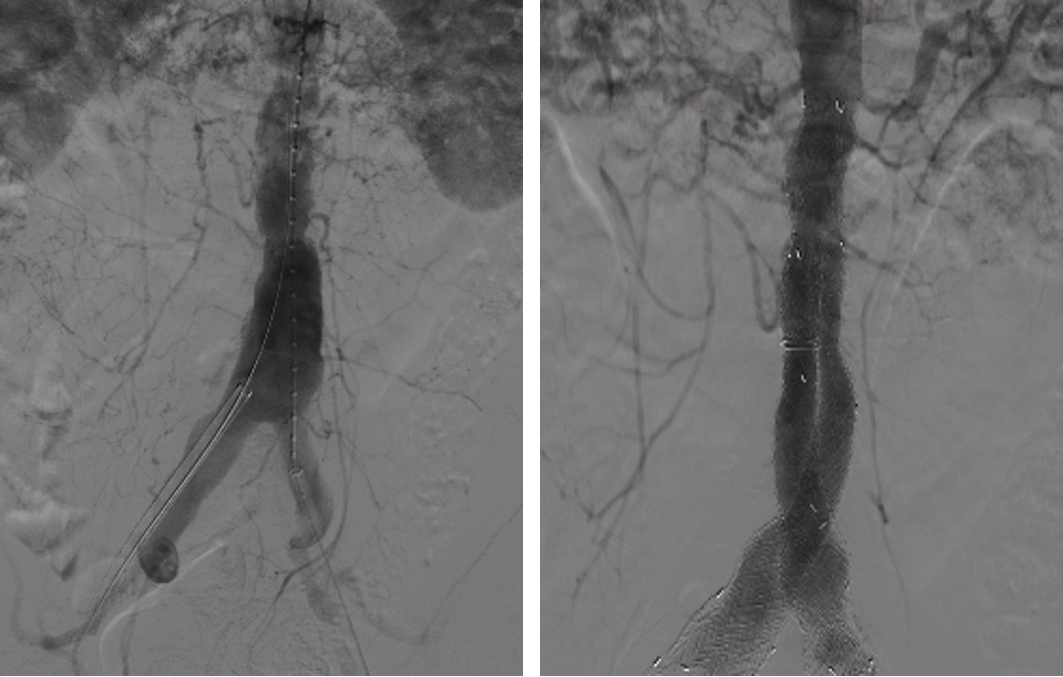

①腹腔干栓塞的可行性

通过67例患者回顾性研究,随访3年显示栓塞组内脏缺血发生率<3%,通畅率保持90%,证实腹腔干栓塞后肝脏和脾脏仍可通过侧支循环(如肠系膜上动脉与胃左动脉吻合)维持血供,为技术改进提供实证支持。

临床意义:简化手术设计,降低手术复杂度,降低脊髓缺血风险。